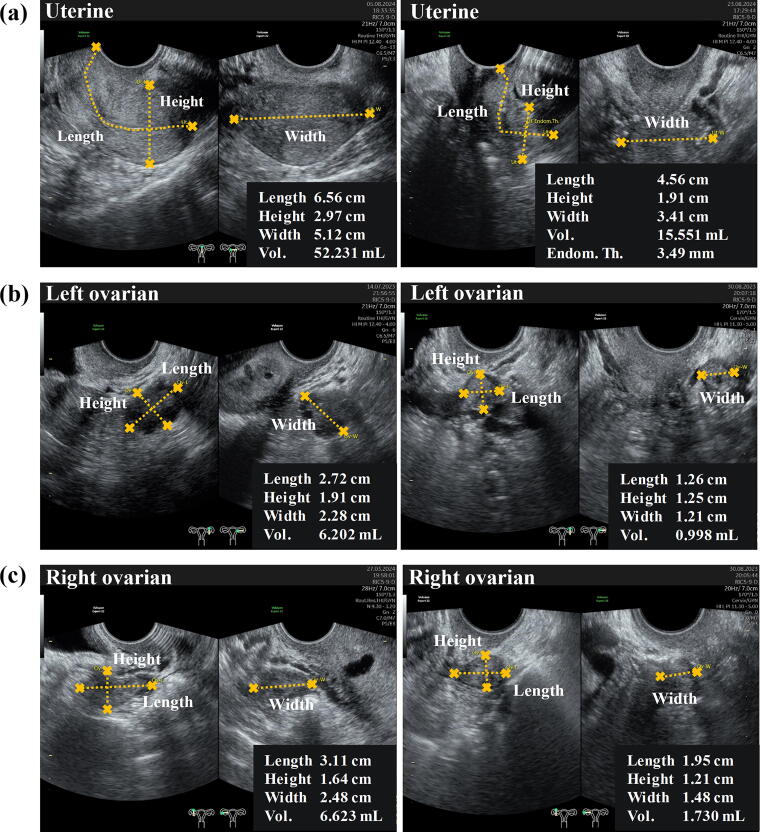

Methods: This research was a retrospective study employing 500 ultrasonography results from various gynecological examinations conducted between 2021 and 2024. The ultrasound record serves as a basis for diagnosis and the definition of inclusion criteria. A morphometric analysis will be performed on the uterus and ovaries of the subject.

Results: The study sample comprised 121 healthy women from reproductive age to menopause, examined using ultrasonography. Significant differences in uterine volume (p < 0.05) were observed between the 21-30 age group and the 31-40, 41-50, 51-60, and >60 age groups. Furthermore, differences in ovarian volume were observed between the right and left ovaries, as well as between women of reproductive age and those who are menopausal.